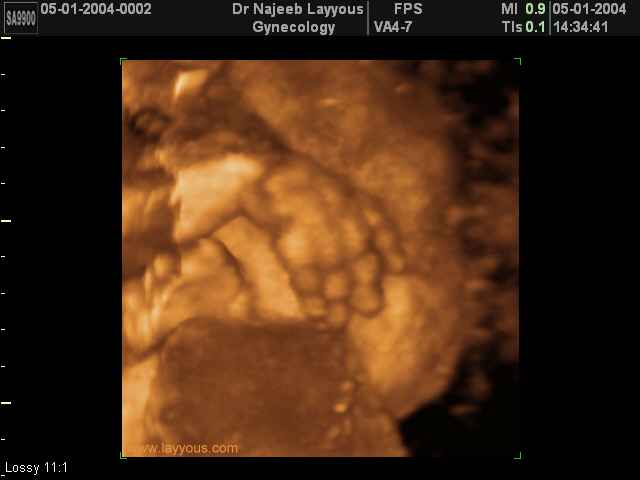

- تصرفات الجنين داخل الرحم

- صور لأعضاء الجنين

- صور لأطراف الجنين

- صور لتصرفات الجنين داخل الرحم

صور لأطراف الجنين بجهاز الالتراساوند ثلاثي الأبعاد | الدكتور نجيب ليوس